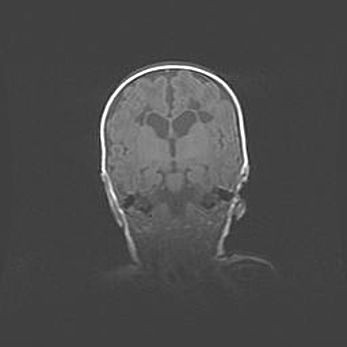

Церебральная ишемия II.

Возраст: 5 дней

Вес: 3400 г

Пол: женский

Окружность головы: 35 см

Срок гестации: 39 недель

Церебральная ишемия – это заболевание, характеризующееся недостаточностью (гипоксией) либо полным прекращением (аноксией) снабжения мозга кислородом по причине закупорки одного или нескольких сосудов. Это приводит к  что метаболическим расстройствам различной степени тяжести в тканях головного мозга, развитию коагуляционных некрозов и гибели нейронов.